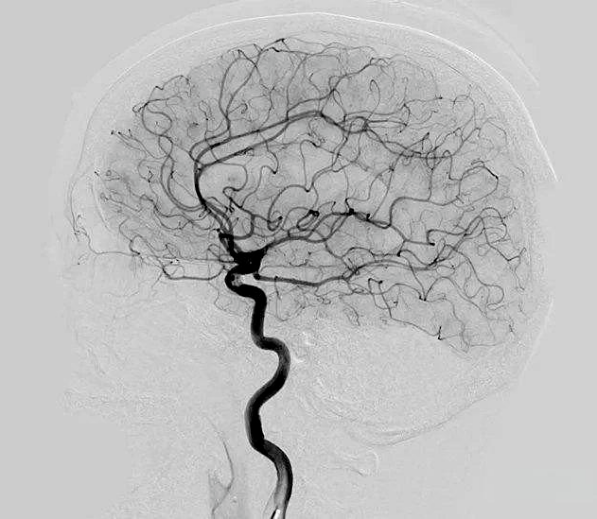

『护理科普』股动脉脑血管造影术后护理的“全流程防线”

当股动脉穿刺的导管完成脑血管造影的“使命”,患者的术后康复便进入了十二病区护理团队的“精细战场”。从穿刺点的每一次按压到足背动脉的每一次触摸,从造影剂的排泄监测到神经功能的动态评估等为患者筑牢术后安全防线。